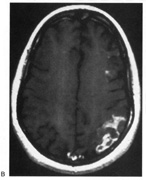

HEMIACHROMATOPSIA.

Achromatopsia in the contralateral hemifield alone can follow unilateral right or left occipital lesions (Fig. 18). Patients are typically asymptomatic until the defect is demonstrated on examination.234,235 Hemiachromatopsia is usually associated with a superior quadrantanopia;234,235,241 therefore, the color defect is only demonstrable in the remaining inferior quadrant. The preserved color vision in the ipsilateral hemifield allows normal or near-normal performance on centrally viewed tests of color vision such as pseudoisochromatic plates. The incidence of hemiachromatopsia is probably underestimated, given its asymptomatic nature and the failure of routine clinical color tests to detect its presence.

Fig. 18. Magnetic resonance imaging scan of patient with stroke causing a right hemiachromatopsia as well as partial superior quadrantanopia.